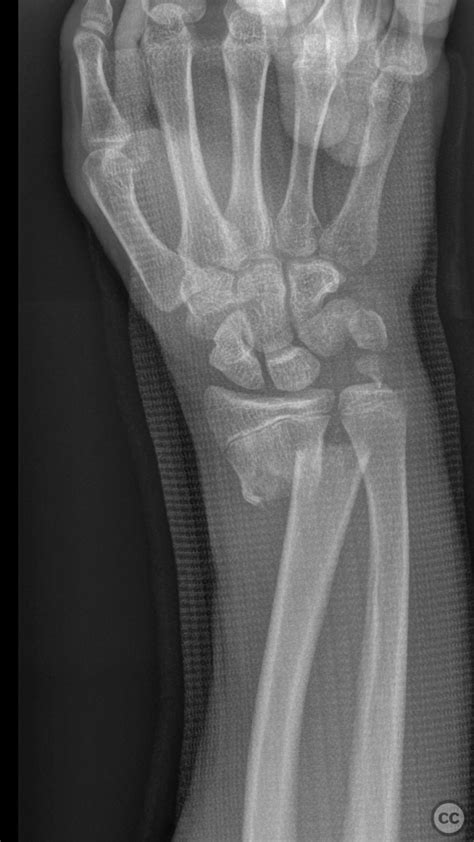

Alright, let’s kick things off by really understanding what we’re up against when we talk about distal radius fractures . These aren’t just any old broken bones; they’re incredibly common, making up a huge chunk of all fractures treated in emergency rooms worldwide. Typically, they happen when you try to break a fall with an outstretched hand, sending all that impact force right up your arm to your wrist. Think about slipping on ice, falling off a bike, or even just a clumsy step – bam , your wrist takes the hit. What’s especially tricky about distal radius fractures is the complex anatomy of the wrist joint. It’s not just a simple hinge; it’s a marvel of engineering with multiple small bones and ligaments all working together for a huge range of motion. When the distal radius, which is the larger of the two forearm bones and crucial for wrist movement, breaks, it can disrupt this delicate balance. We often categorize these fractures by patterns: Colles fractures , where the bone breaks with the fragment tilting upwards (dorsally); Smith fractures , which are less common, where the fragment tilts downwards (volarly); and Barton fractures , which involve the joint surface itself, sometimes with dislocation. Each type presents its own unique challenge, but they all share the common goal of needing precise reduction and stable fixation to ensure a good functional outcome. The AO classification system , which is a comprehensive way to describe fractures based on location, severity, and joint involvement, helps surgeons speak a common language and plan treatment strategies more effectively. Knowing these classifications helps us appreciate why a tailored approach, like the Kapandji technique, is often necessary. Without proper management, these fractures can lead to long-term pain, stiffness, and even arthritis, significantly impacting a person’s quality of life. That’s why getting it right the first time is so crucial, and why techniques like Kapandji’s have become so valuable in the orthopaedic toolkit. The challenge with these injuries isn’t just getting the bones to stick back together; it’s about restoring the intricate biomechanics of the wrist so that patients can regain their full range of motion, grip strength, and overall function. It’s a big ask, but with the right approach, it’s totally achievable.

Alright, let’s pull back the curtain and see exactly what goes down during a Kapandji technique procedure for a distal radius fracture . This isn’t just about sticking wires in; it’s a meticulously planned surgical journey designed to achieve optimal results. First up, pre-operative planning is paramount. This involves a thorough assessment of the patient, understanding their medical history, and, most importantly, getting high-quality imaging – X-rays, and sometimes a CT scan – to fully appreciate the fracture pattern. Surgeons will meticulously analyze the displacement, angulation, and involvement of the joint surface. This helps determine if Kapandji is the best fit and how many pins will be needed and their ideal trajectory. Once the decision is made, the patient is prepared for surgery. Anesthesia is typically regional (like a nerve block) or general, ensuring the patient is comfortable and pain-free. The patient is usually positioned supine (on their back) on the operating table, with the arm extended on a hand table, allowing full access to the wrist. Crucially, a tourniquet is applied to the upper arm to create a bloodless field, which significantly improves visibility for the surgeon. Now, the real artistry begins with reduction maneuvers . This involves gentle traction applied to the hand, often manually, to distract the fracture fragments. The surgeon then uses specific manual manipulations, sometimes with the help of a bone clamp or K-wire, to restore the correct length and alignment of the distal radius. This is often done under fluoroscopic guidance – a real-time X-ray machine – which acts as the surgeon’s eyes, ensuring every manipulation is precise. Once a satisfactory reduction is achieved, it’s time for pin insertion . This is where the Kapandji technique truly shines. Typically, two to three small K-wires are inserted percutaneously (through small skin punctures, avoiding large incisions). The entry points are usually on the dorsal (back) or radial (thumb side) aspect of the wrist, depending on the fracture pattern. The wires are advanced into the fracture site itself , acting as levers or